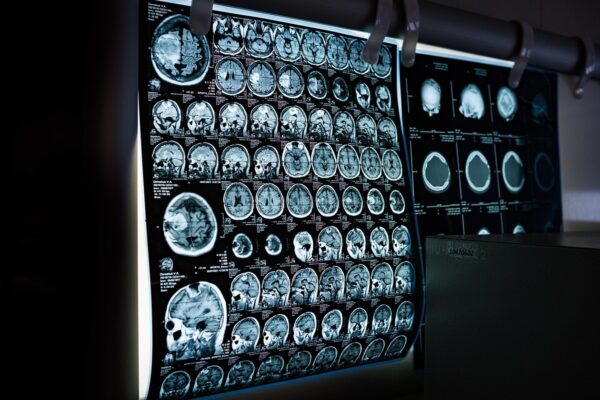

Енні Седорік страждала від хронічного болю та деформацій обличчя, поки лікарі не діагностували акромегалію – рідкісне гормональне захворювання, спричинене пухлиною мозку. У США 28-річна Енні Седорік протягом двох років марно шукала причину різкого погіршення здоров’я: постійного болю, деформацій обличчя, порушень менструального циклу та проблем із суглобами. Лише після численних консультацій, двох операцій на щелепі та…